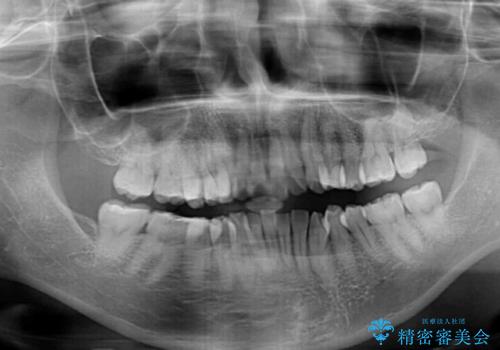

奥歯の咬み合わせを見ると、上顎が下顎に対して相対的に前方にありました。

口元の閉じにくさを改善するためには、上顎臼歯を後方に移動させた咬み合わせにする必要があります。

インビザライン単体で改善することも可能ですが、達成する可能性が高くないため、カリエールディスタライザーという補助装置を併用して、より確実性を上げることとしました。

奥歯の咬み合わせを改善しながら、並行してインビザラインで歯列を整えることとしました。